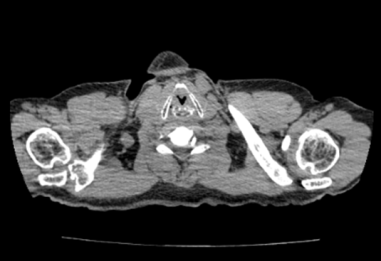

Paciente quien se evalúa en área de consulta, y se solicita tomografía computarizada (TC) de cuello y tórax (Figura 1 y 2), donde se observa obliteración parcial del lumen laríngeo, sin erosión de sus cartílagos, además ganglios linfáticos cervicales bilaterales menores de 1 cm, y a nivel torácico enfermedad bulosa extensa a predominio de lóbulos superiores, sin lesiones nodulares sugestivas de extensión secundaria. Se decide realizar laringoscopia directa más toma de biopsia, en área quirúrgica, donde se evidencia como hallazgos, una tumoración exofítica, friable, que ocupa la cuerda vocal izquierda con infiltración a ambos repliegues aritenoepiglóticos.